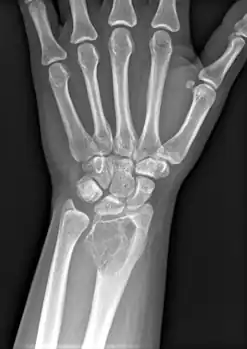

X-ray of a giant-cell bone tumor in the head of the fourth metacarpal of the left hand

On X-ray, giant-cell tumors (GCTs) are lytic/lucent lesions that have an epiphyseal location and grow to the articular surface of the involved bone.[11] Radiologically the tumors may show characteristic 'soap bubble' appearance.[12] They are distinguishable from other bony tumors in that GCTs usually have a nonsclerotic and sharply defined border. About 5% of giant-cell tumors metastasize, usually to a lung, which may be benign metastasis,[13] when the diagnosis of giant-cell tumor is suspected, a chest X-ray or computed tomography may be needed. MRI can be used to assess intramedullary and soft tissue extension.